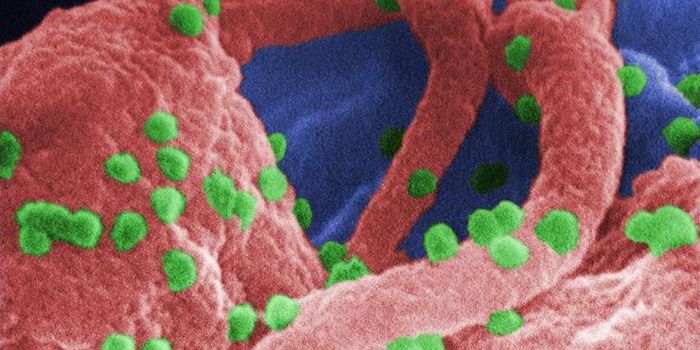

SEP 20, 2021Genetics & GenomicsHuman immunodeficiency virus (HIV) is a retrovirus, which is a type of virus that can write its genetic material into th ...